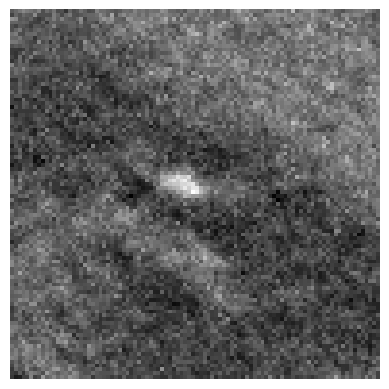

Refer to caption

(a)

(b)

(c)

(d)

Figure 3: Representation of generated features by DINO-LG model trained with label-guided approach and standard DINO training. Figure (a)𝑎(a)( italic_a ) represents a CT slice having calcified area and (b)𝑏(b)( italic_b ) shows annotated area for calcification. Figure (c)𝑐(c)( italic_c ) and (d)𝑑(d)( italic_d ) represent visualization of overlay self-attention maps are generated by standard DINO model and DINO-LG model, respectively.